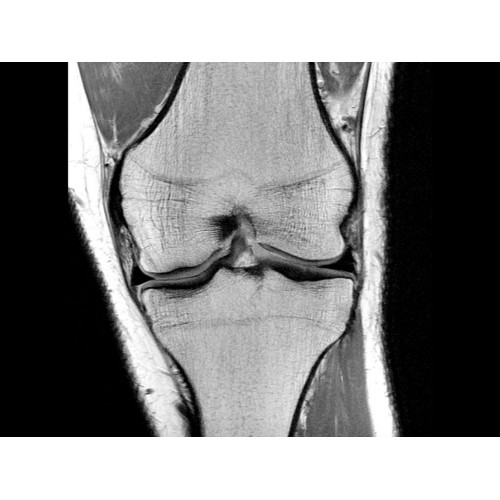

МРТ аппарат GE Optima MR450w 1.5T

МР-томограф с широким туннелем Optima MR450w является настоящей рабочей лошадкой и может эффективно обслуживать большее число пациентов. Томограф обеспечивает одновременно удобство пациента, продуктивность работы, отличное качество изображения. В этой МРТ-системе инженерам компании удалось без компромиссов совместить необходимый объем перемещения с удивительно высоким качеством изображения.

Благодаря принципиально новым технологиям мы расширили возможности МР-томографов с широкими туннелями, совместив непревзойденное качество изображений с высокой производительностью при широком — 50 см — поле зрения.

МР-томограф Optima MR450w позволяет получать изображения исключительно высокого качества, которые помогают установить диагноз. Чтобы удовлетворить ожидания клиентов в отношении высокого качества, в МР-томографе Optima MR450w были сохранены дополнительные возможности платформы Discoverу, привнесшие в его работу универсальность и мощь.

• РЧ-катушки, оптимизированные для исследования конкретных участков тела — элементы катушек высокой плотности располагаются вокруг исследуемых участков тела и при необходимости обеспечивают расширенный охват и оптимальное качество изображений при каждой процедуре.